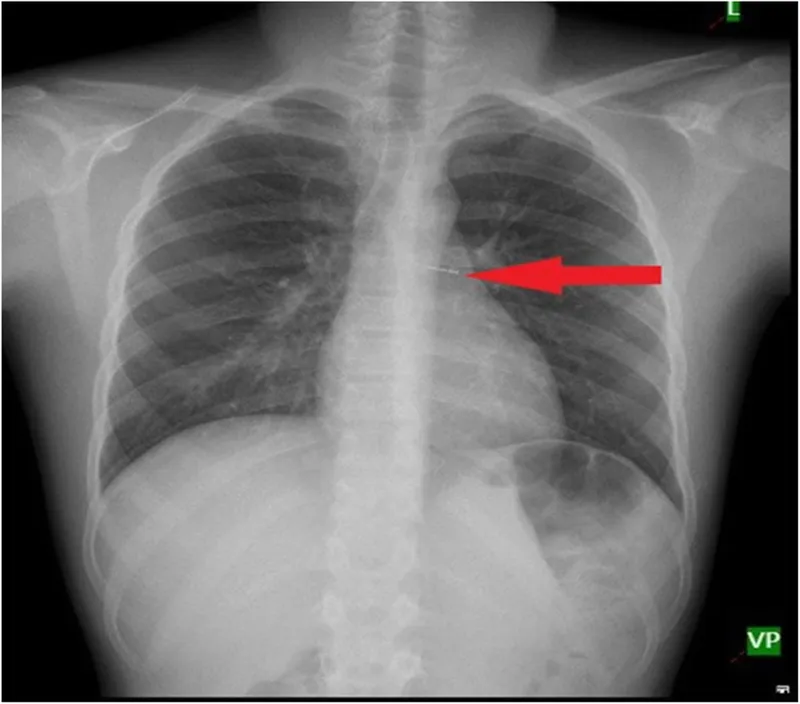

- Chest X-ray (PA & Lateral):

- Radio-opaque FB visible.

- Indirect signs for radiolucent FB: Unilateral hyperinflation (ball-valve), mediastinal shift (expiratory film), atelectasis/collapse.

- Inspiratory/Expiratory films or lateral decubitus views (affected side down) can accentuate findings.

- Normal CXR in 15-30% of cases.

- Expiratory chest X-ray: Shows air trapping (hyperinflation) & mediastinal shift.

- Ball-valve obstruction causes unilateral hyperinflation; complete obstruction causes atelectasis.